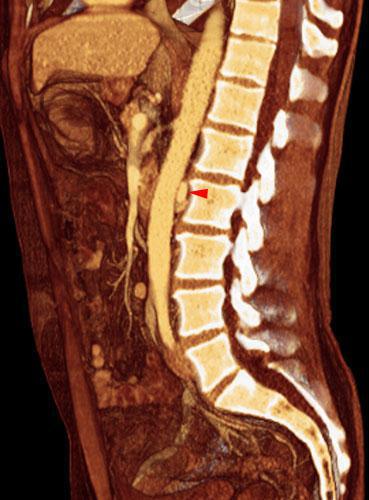

VR seccional. Visión sagital izquierda. AngioTC renal visualizándose una vena renal izquierda de situación retroáortica (punta de flecha), pasando en el espacio entre aorta abdominal y cuerpo vertebral lumbar